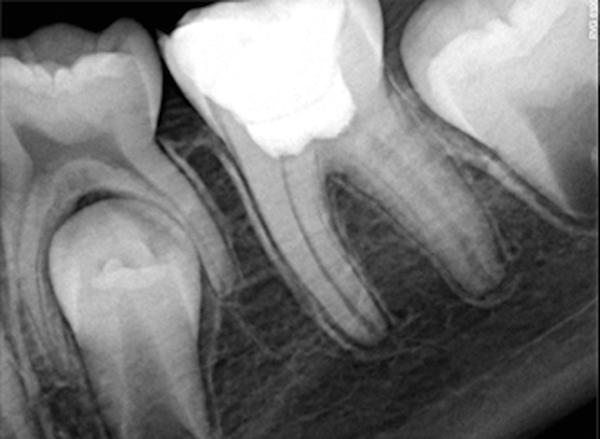

Figure 4. AND Figure 5. Before and after radiographs of bioceramic sealer hydraulically moved with the gutta-percha point. Note that the cold hydraulic technique results in lateral canal “puffs” similar to the warm vertical technique. Courtesy of Dr. Mohammed A. Alharbi.

Figure 4

Figure 5